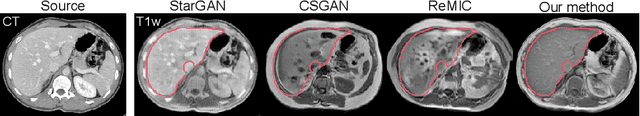

Paired multi-modality medical images, can provide complementary information to help physicians make more reasonable decisions than single modality medical images. But they are difficult to generate due to multiple factors in practice (e.g., time, cost, radiation dose). To address these problems, multi-modality medical image translation has aroused increasing research interest recently. However, the existing works mainly focus on translation effect of a whole image instead of a critical target area or Region of Interest (ROI), e.g., organ and so on. This leads to poor-quality translation of the localized target area which becomes blurry, deformed or even with extra unreasonable textures. In this paper, we propose a novel target-aware generative adversarial network called TarGAN, which is a generic multi-modality medical image translation model capable of (1) learning multi-modality medical image translation without relying on paired data, (2) enhancing quality of target area generation with the help of target area labels. The generator of TarGAN jointly learns mapping at two levels simultaneously - whole image translation mapping and target area translation mapping. These two mappings are interrelated through a proposed crossing loss. The experiments on both quantitative measures and qualitative evaluations demonstrate that TarGAN outperforms the state-of-the-art methods in all cases. Subsequent segmentation task is conducted to demonstrate effectiveness of synthetic images generated by TarGAN in a real-world application. Our code is available at https://github.com/2165998/TarGAN.